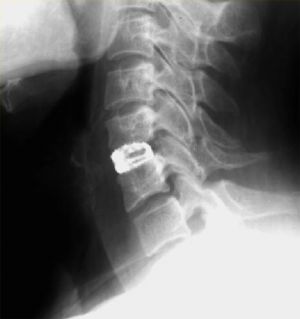

Лечение шейного стеноза хирургическим методом заключается в выполнении декомпрессии позвоночного канала и спинного мозга (т.е. освобождении его от сдавления(компрессии)). В большинстве случаев операция заключается в удалении мп грыжи диска и установке в межтеловое пространство (между двумя смежными телами позвонков) кейджа. (Рис. 4). В настоящее время наиболее современным заменителем диска является искусственный диск. Наиболее близким по строению и функции к обычному диску является искусственный диск «М6-С». (Рис.5) Так же как и настоящий диск указанный имплант состоит 2-х частей: искусственного ядра, обеспечивающего осевое сжатие, и кольца из волокнистого материала, обеспечивающего подвижность с контролируемой амплитудой и с шестью степенями свободы. (Рис.6) Такая конструкция обеспечивает физиологическую подвижность позвоночно-двигательного сегмента и, возможно, предотвращение и отсрочку дальнейшей дегенерации дисков на уровне соседних позвонков. Биомеханические испытания искусственного диска М6-С подтвердили качество подвижности, эквивалентное человеческому диску.